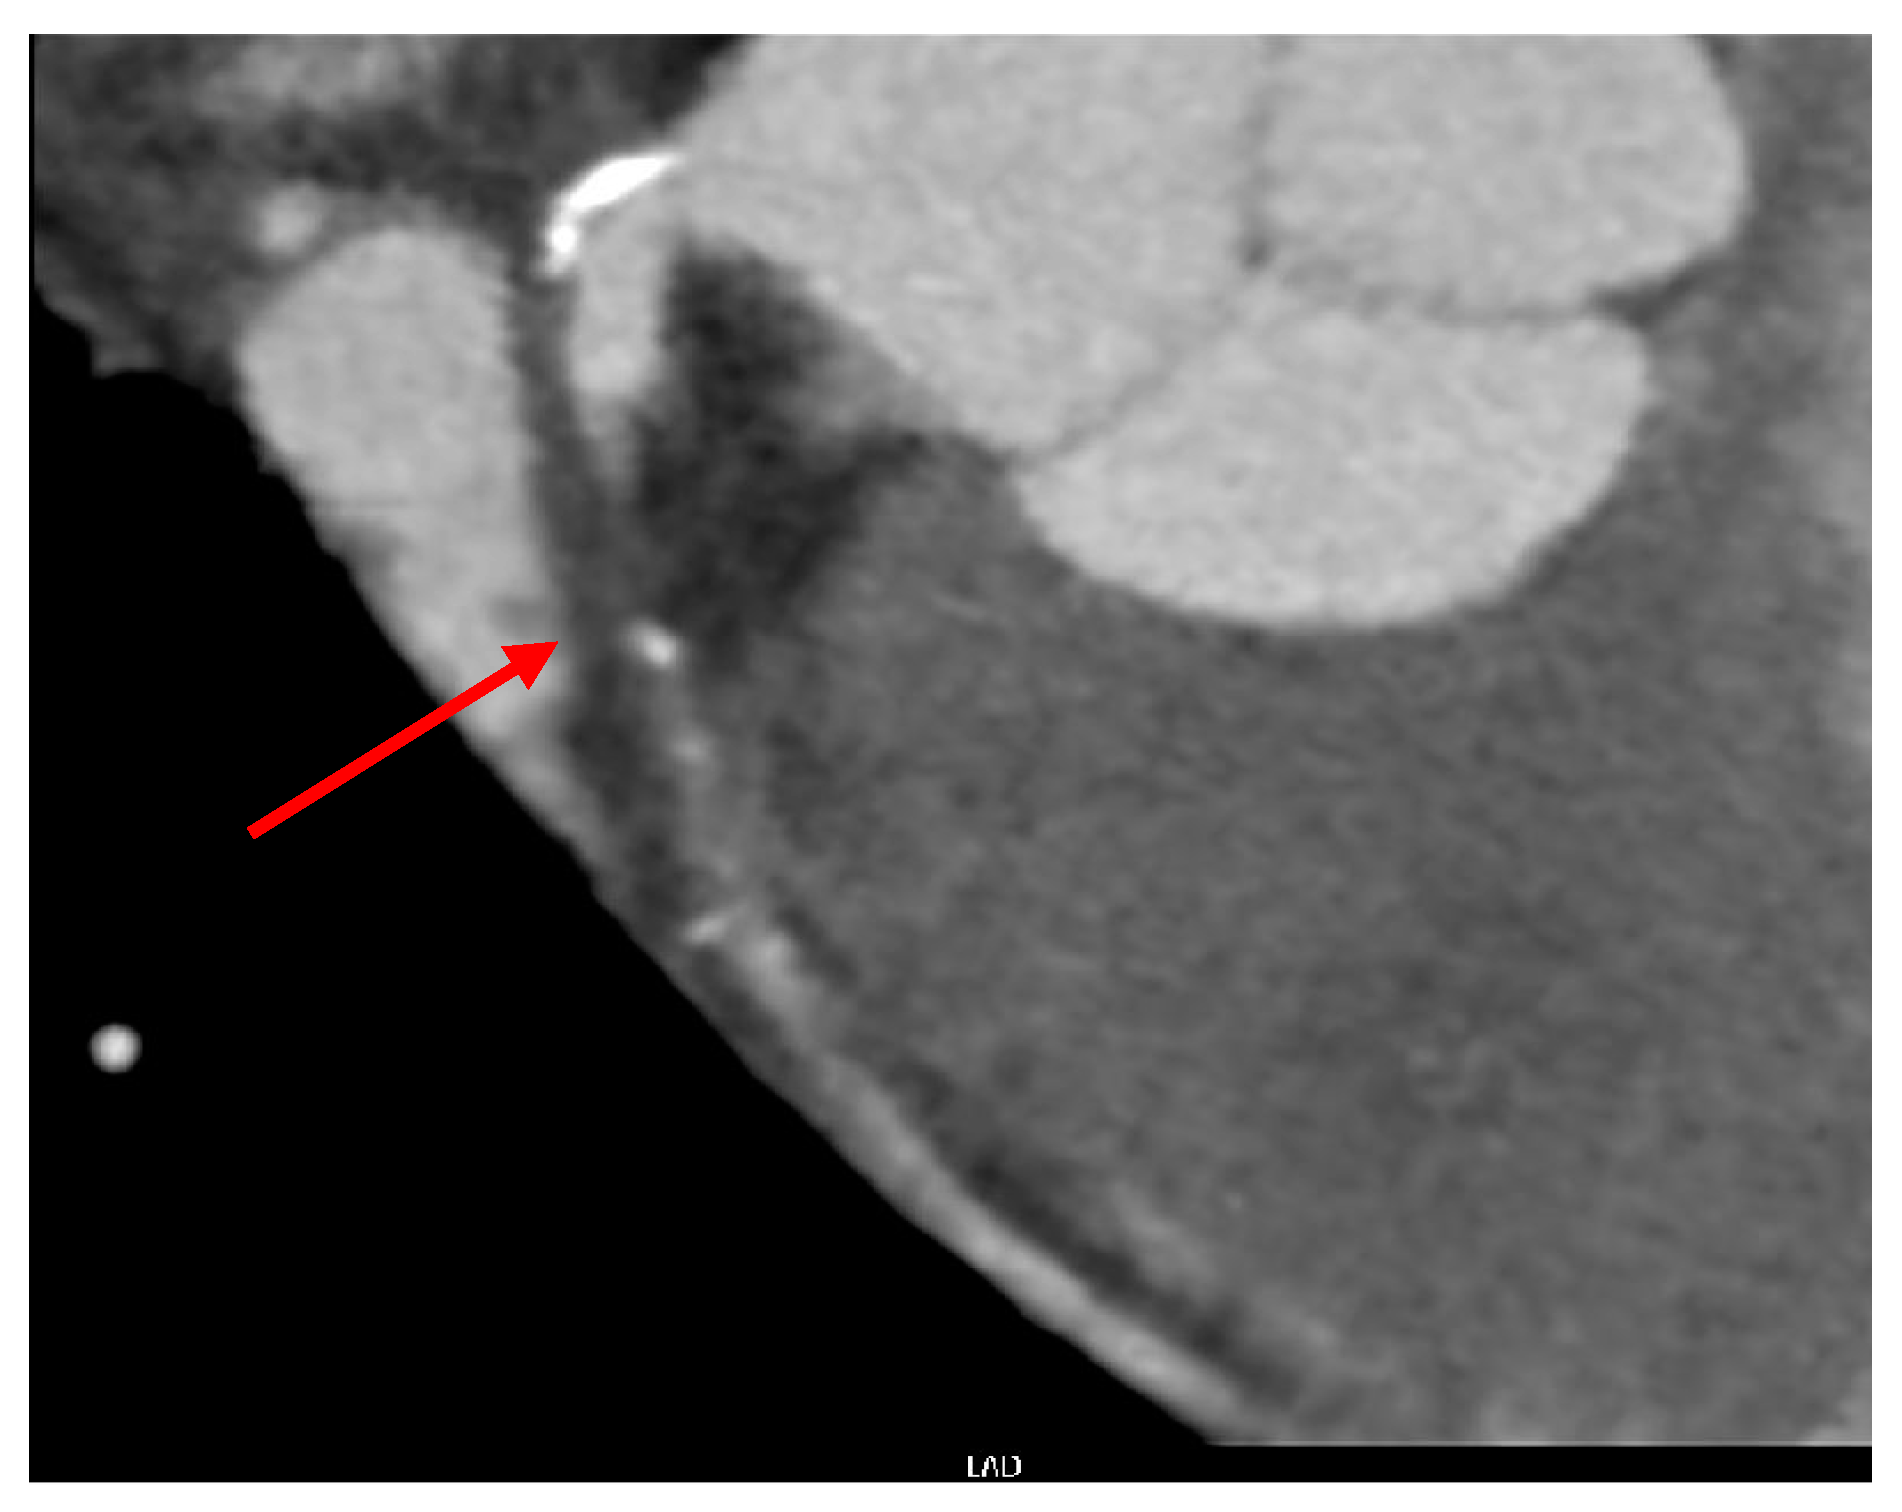

2. Case Presentation